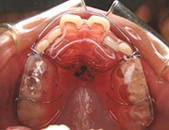

全て乳歯です。反対咬合です。まだ幼児なので、お子様にかかる負担などをよく考えた上で、治療します。

反対咬合です。